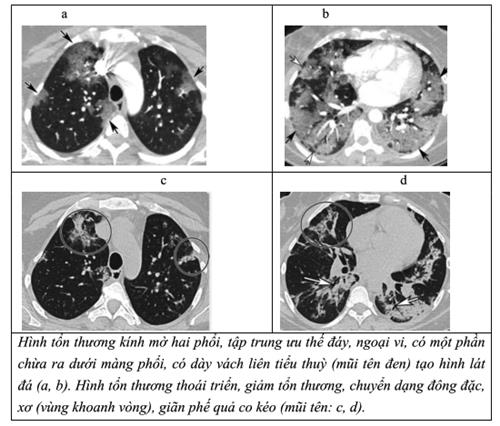

4.6. Chụp CT-Scan

- Tổn thương kính mờ đa ổ ở vùng đáy và ngoại vi hai bên phổi. Tổn thương lát đá.

- Tổn thương kính mờ và đông đặc ở vùng đáy và ngoại vi hai bên phổi.

- Phát hiện các trường hợp tắc mạch phổi.

- Phân loại CO-RADS (xem Phụ lục 7).

Hình 2. CLVT ngực người bệnh nữ, 36 tuổi, nhiễm COVID-19.